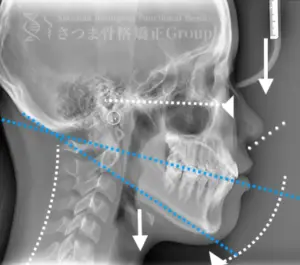

渋谷TMJ歯科クリニックでは、頭蓋および頸椎の歪みが顎位(あごの位置)と咬合(噛み合わせ)の乱れを引き起こし、その結果として顔の歪み、顎関節症、食いしばり、ストレートネックによる強い肩こり、さらには自律神経の乱れへとつながると考えています。

これらの問題を正確に評価するため、当院では セファロシステムによるレントゲン撮影(X-ray images) を行っています。

セファロ撮影によって 顎関節・頭蓋骨・頸椎の位置関係を客観的に可視化でき、施術前の状態を科学的に把握することが可能となります。